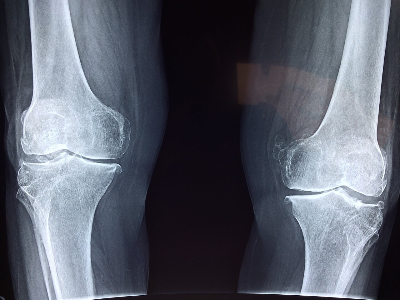

골수염 진단에는 병력 검토, 신체검사, 영상 검사(엑스레이, MRI 또는 CT 스캔 등), 실험실 검사(혈액 배양 또는 뼈 생검 등)가 복합적으로 사용되는 경우가 많습니다.